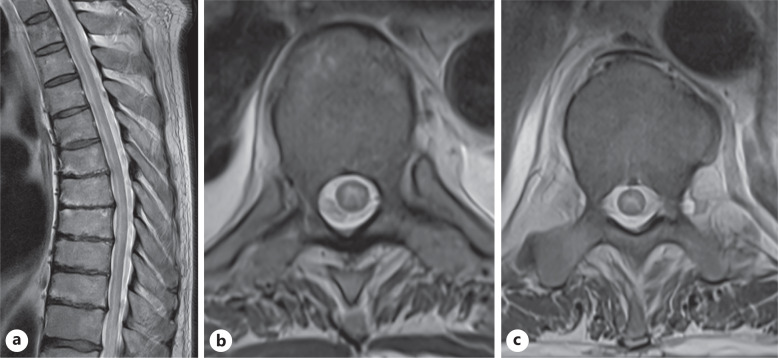

Case presentation: A previously healthy man in his 70s presented with headache, fever, and confusion, followed by a seizure and persistent hiccoughs. MRI revealed brainstem involvement and extensive transverse myelitis. Cerebrospinal fluid (CSF) analysis showed inflammatory features, but testing for AQP4, MOG, and GFAP antibodies was initially negative. He was treated with intravenous corticosteroids and plasma exchange, after which serum GFAP-IgG was weakly positive, though CSF remained negative. His condition improved with immunotherapy, but significant lower limb weakness persisted. Based on clinical and radiological findings, we hypothesize that tanycytes - specialized glial cells in the area postrema - may be an additional immune target in GFAP encephalitis.